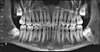

Nous offre un diagnostic précis, très efficace et immédiat pour :

- La recherche des foyers infectieux,

- L'anatomie exacte de certaines dents,

- Et aussi la réalisation de radios panoramiques et de téléradiographies de profil.